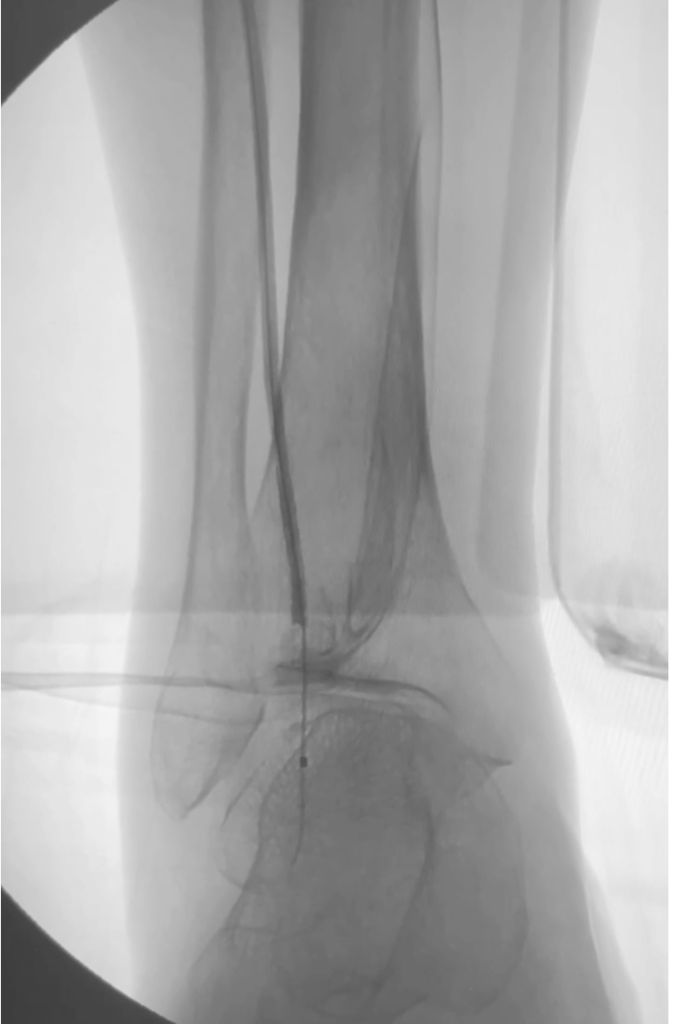

Angioplastia de arterias

Cateterismo de minima invasion en las arterias, busca mediante balones especiales abrir la circulación permitiendo pase la sangre y continue la irrigación con oxigeno para salvar las piernas.